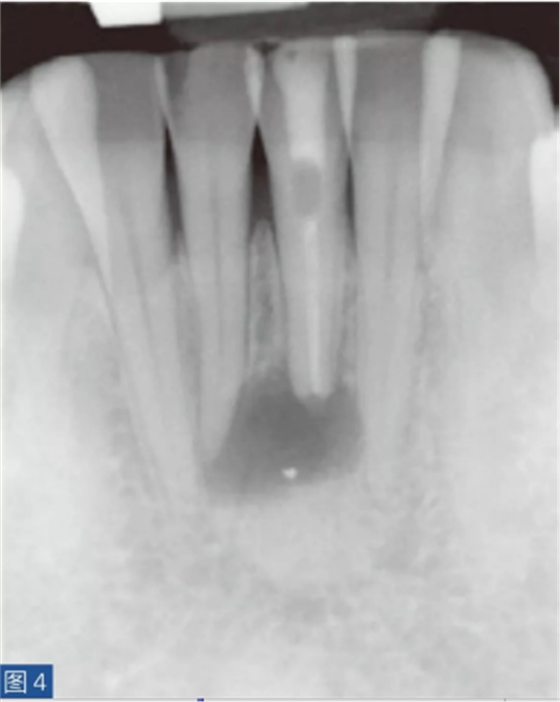

牙齒無(wú)癥狀的根尖周炎(圖4 和5)是由牙髓壞死引起的,并且通常是在癥狀性根尖周炎之后發(fā)生。因此,對(duì)冷、熱刺激和牙髓電活力測(cè)試無(wú)反應(yīng)。叩診無(wú)或者引起輕微的疼痛。如果骨皮質(zhì)已經(jīng)發(fā)生改變并且涉及到口腔軟組織,則觸診可引起輕微不適。放射學(xué)檢查,可能出現(xiàn)硬骨板不連續(xù)(破壞)以及根尖周和牙間組織的廣泛性破壞。

圖4:31 牙齒AAP。術(shù)前X線片?;颊咴V叩診和觸診時(shí)有輕微疼痛。

圖5:31 牙齒AAP。根管再治療12 個(gè)月后。